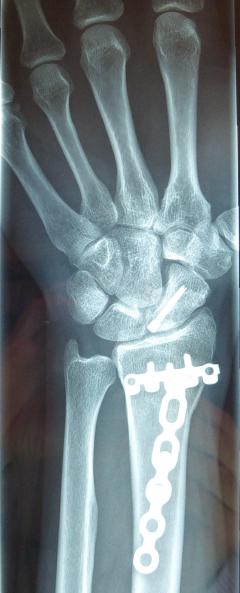

Η αντιμετώπιση της ψευδάρθρωσης του σκαφοειδούς είναι πάντοτε χειρουργική. Με ραχιαία ή παλαμιαία προσπέλαση αποκαθίσταται ο άξονας του σκαφοειδούς και σταθεροποιείται το σκαφοειδές με ειδική βίδα ή βελόνες, με παράλληλη τοποθέτηση οστικών μοσχευμάτων. Μπορεί επιπλέον να γίνει και οστεοτομία κλειστής σφήνας του περιφερικού άκρου της κερκίδος. Στις περιπτώσεις άσηπτης νέκρωσης το μόσχευμα πρέπει να είναι αγγειούμενο – για να προσδώσει αιμάτωση στο νεκρωμένο κεντρικό τμήμα – και λαμβάνεται με μικροχειρουργικές τεχνικές από το περιφερικό τμήμα της κερκίδος ή από άλλα τμήματα του σώματος

Μετεγχειρητικά 1